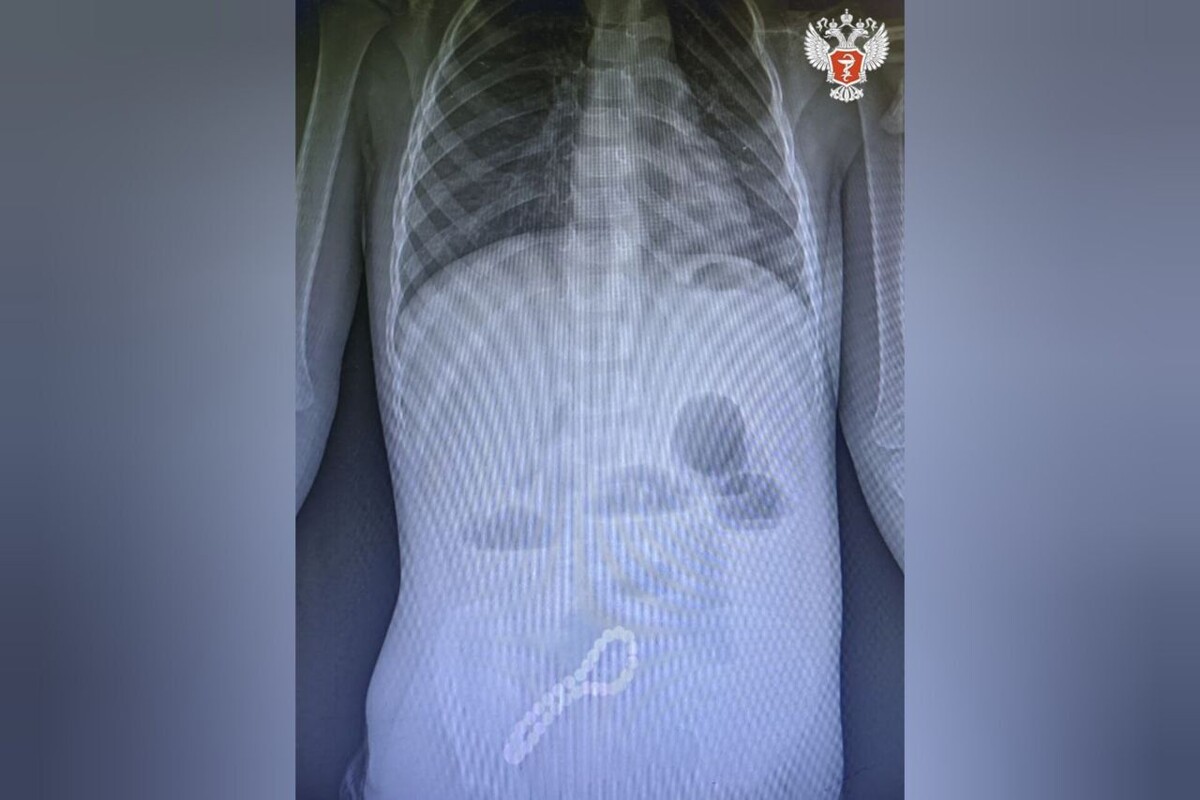

Мальчика доставили в Областную детскую клиническую больницу с жалобами на проблемы с желудочно-кишечным трактом. Рентген показал наличие в кишечнике инородного тела, требовавшего удаления.

Хирурги приняли решение провести операцию. Для извлечения браслета была выполнена минилапаротомия — хирургическое вмешательство через небольшой разрез на передней брюшной стенке. Как пояснил главный внештатный хирург министерства здравоохранения региона Олег Ларькин, магниты браслета сцепились между собой, вызвав слипание петель кишечника.